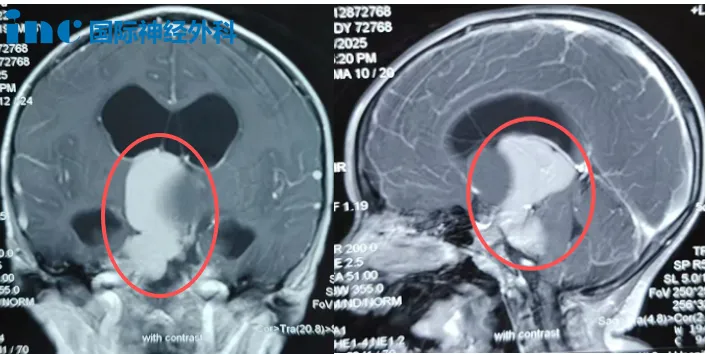

术前MRI,小安脑中的“大虫子”

这条“虫”潜伏在小安的颅内,引发持续头痛、呕吐,导致发育迟滞和四肢无力。影像检查显示,肿瘤从鞍上延伸至第三脑室和桥小脑角区,并已引发脑积水。随着“虫子”向“生命禁区”脑干生长,小安的症状日益加重:呕吐变得剧烈,头痛持续不断,右腿活动也逐渐不灵,走路时常绊倒。